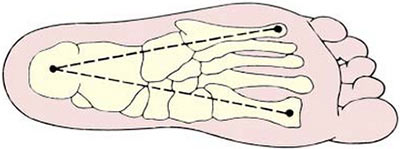

La voute plantaire forme un ensemble biomécanique composé d’une arche antérieure transverse, une arche longitudinale médiale et une arche longitudinale latérale.

Cette voûte comporte trois points d’appui, les premières et cinquièmes têtes métatarsiennes et le calcaneus.

Cette architecture plastique avec le système musculaire et aponévrotique de ces arches permet la rigidification des structures, la transmission des forces ainsi que l’amortissement des charges et des chocs et la propulsion lors d’un simple pas ou d’un saut.

L’arche antérieure est située au niveau des têtes des métatarsiens qui forment une voûte transversale avec appui du premier et du cinquième métatarsien.

Le rôle du dôme est de supporter l’arche transversaire du pied et par conséquent réduire la pression sur les têtes métatarsiennes.